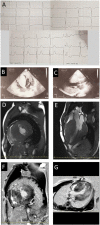

Hypertrophic cardiomyopathy (HCM) is one of the most common hereditary diseases, and it is associated with fatal complications. The clinical heterogeneity of HCM requires risk prediction models to identify patients at a high risk of adverse events. Most HCM cases are caused by mutations in genes encoding sarcomere proteins. However, HCM is associated with rare genetic variants with limited data about its clinical course and prognosis, and existing risk prediction models are not validated for such patients' cohorts. TRIM63 is one of the rare genes recently described as a cause of HCM with autosomal-recessive inheritance. Herein, we present two cases of HCM associated with TRIM63-compound heterozygous variants in young male sportsmen. They demonstrated progressively marked hypertrophy, advanced diastolic dysfunction, a significant degree of fibrosis detected by magnetic resonance imaging, and clear indications for implantable cardioverter-defibrillator. One of the cases includes the first description of TRIM63-HCM with extreme hypertrophy. The presented cases are discussed in light of molecular consequences that might underlie cardiac and muscle phenotype in patients with mutations of TRIM63, the master regulator of striated muscle mass.